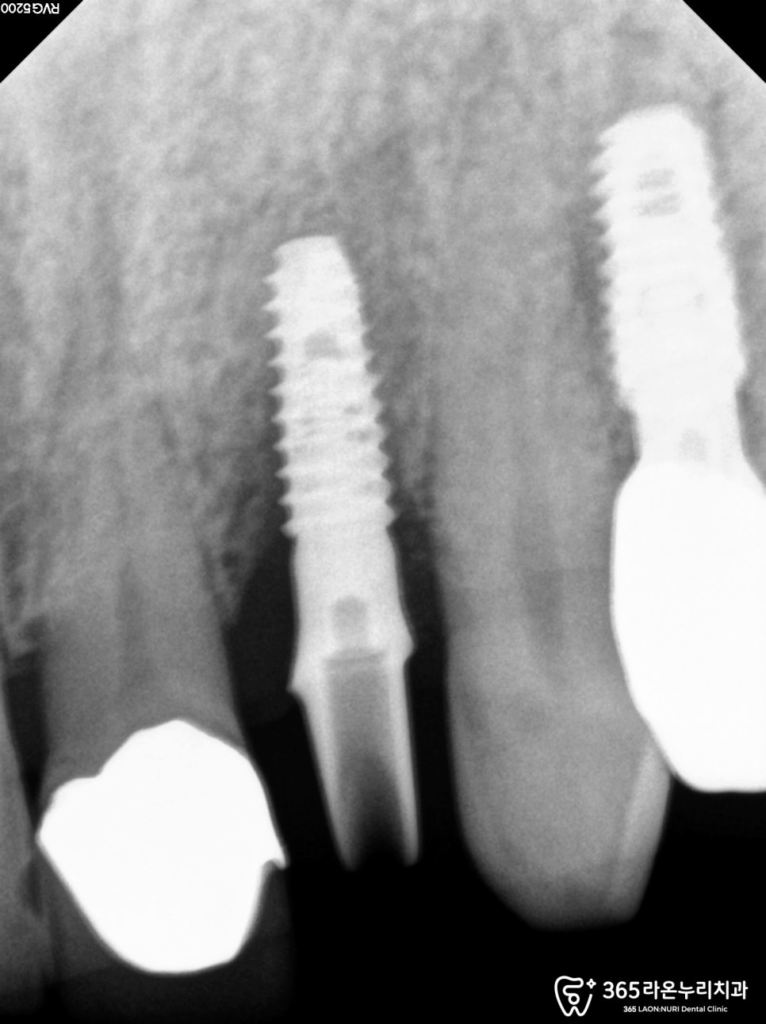

CT를 활용해 주위 치주 조직과

상악동, 하치조 신경, 인접 치아의

치근에 따라 실제 수술 준비를

하는 과정이 있습니다.

임플란트 픽스처는 한 번

식립하면 위치를 수정하기 까다로운

특성 때문에, 더욱

신중한 수술이 필요합니다.

CT 데이터를 이용해

임플란트 식립 위치를

정하게 됩니다.

정확한 식립과 더불어

겉면 뼈를 보강해,

두께와 높이가 최대한

유지되는 모습이 보입니다.